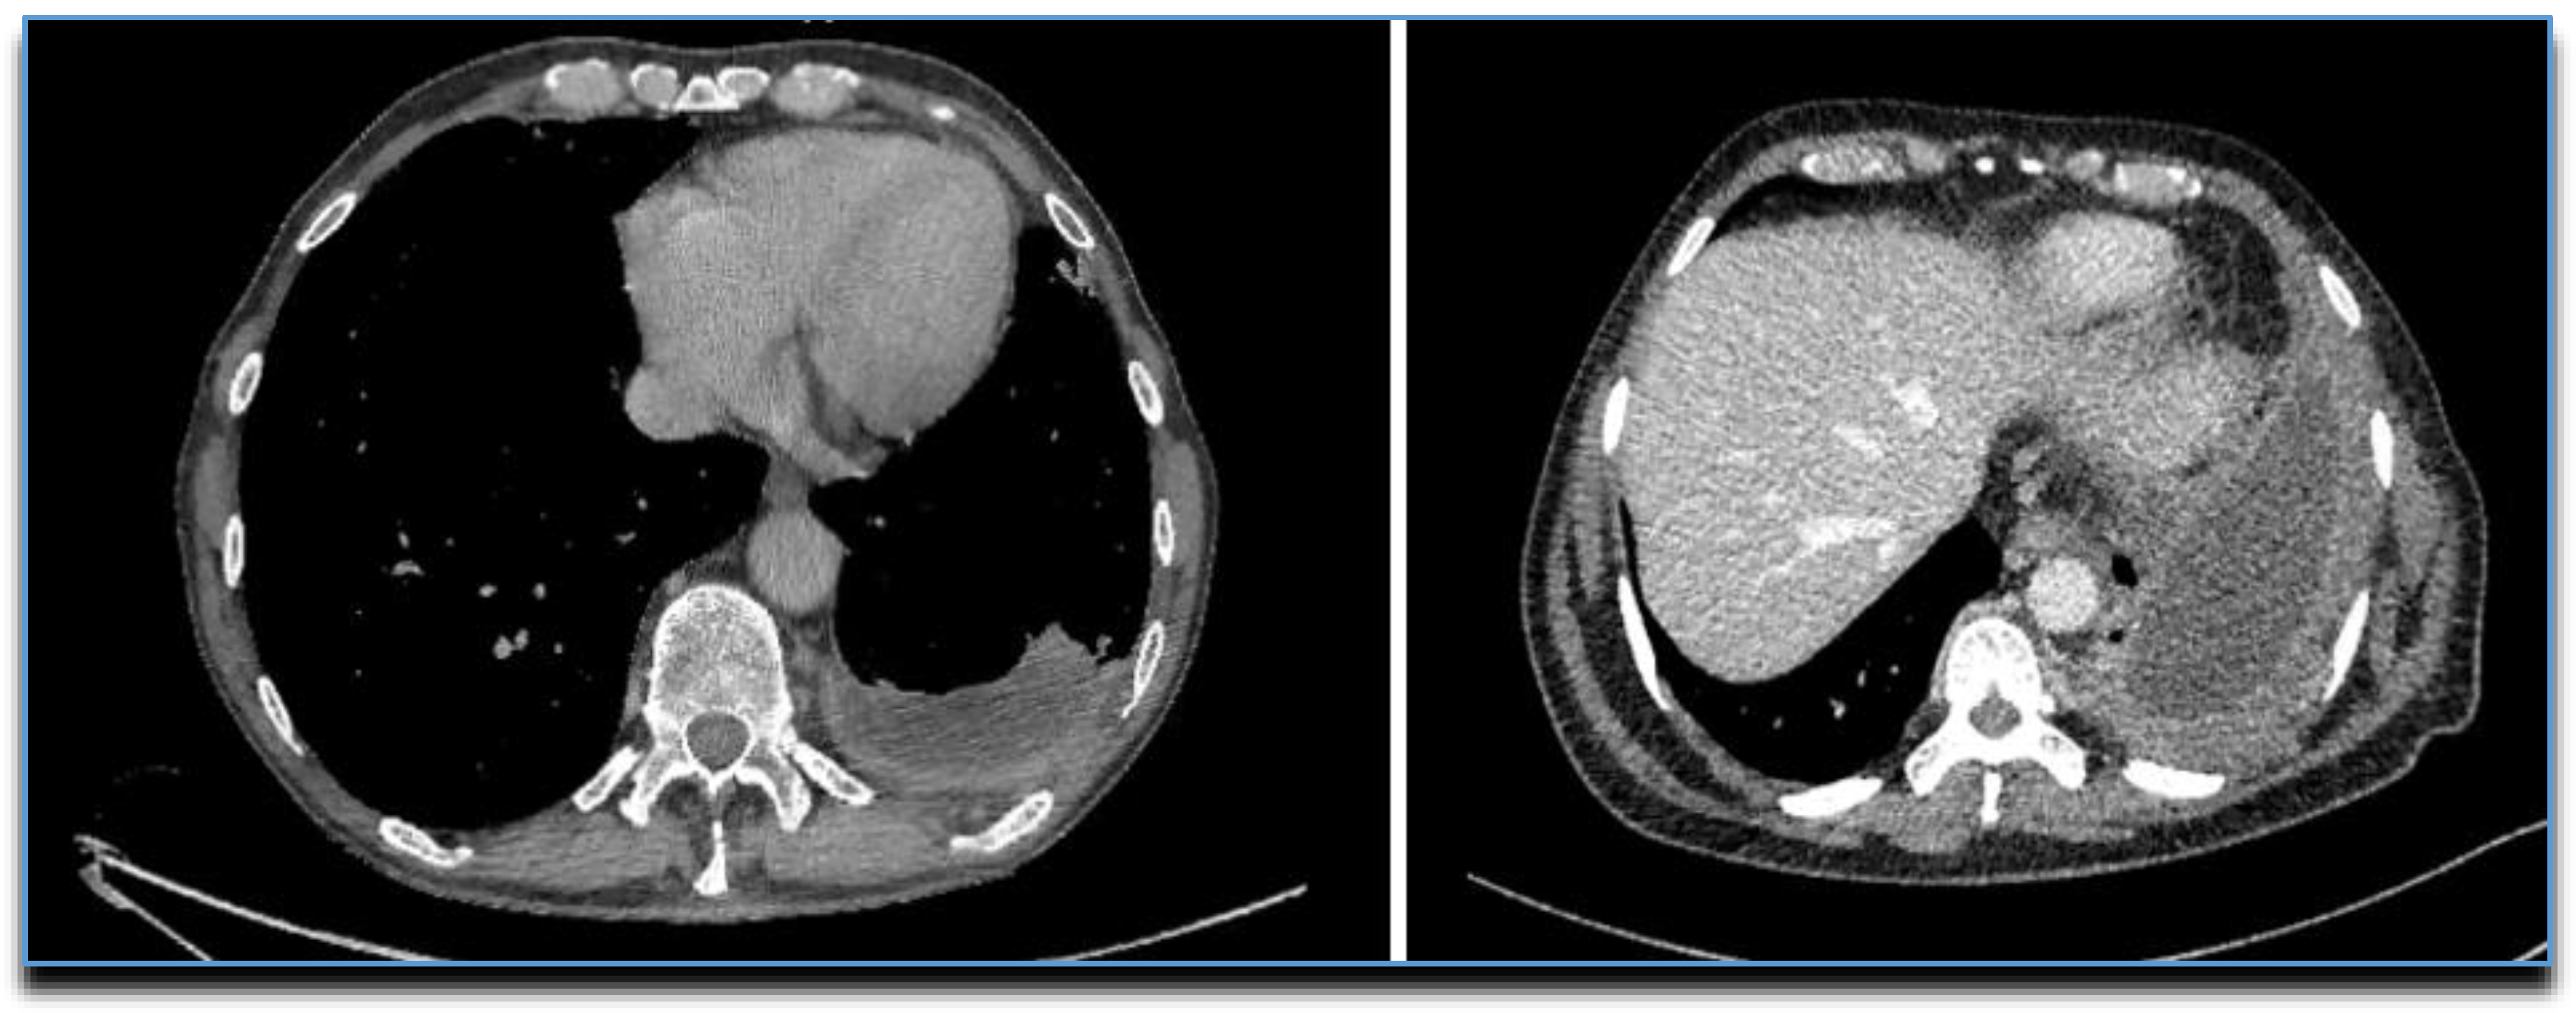

14. CT

- Leung, A.N.; Müller, N.L.; Miller, R.R. CT in differential diagnosis of diffuse pleural disease. Am. J. Roentgenol. 1990, 154, 487–492. [Google Scholar] [CrossRef] [PubMed]

- Duerden, L.; Benamore, R.; Edey, A. Radiology: What is the role of chest radiographs, CT and PET in modern management. In Pleural Disease (ERS Monograph) [Internet]; Maskell, N.A., Laursen, C.B., Lee, Y.C.G., Rahman, N.M., Eds.; European Respiratory Society: Sheffield, UK, 2020; pp. 48–72. [Google Scholar] [CrossRef]

- Tsim, S.; Stobo, D.B.; Alexander, L.; Kelly, C.; Blyth, K.G. The diagnostic performance of routinely acquired and reported computed tomography imaging in patients presenting with suspected pleural malignancy. Lung Cancer 2017, 103, 38–43. [Google Scholar] [CrossRef]

- Arenas, J.; García-Garrigós, E.; Escudero-Fresneda, C.; Sirera-Matilla, M.; García-Pastor, I.; Quirce-Vázquez, A.; Planells-Alduvin, M. Early and delayed phases of contrast-enhanced CT for evaluating patients with malignant pleural effusion. Results of pairwise comparison by multiple observers. Br. J. Radiol. 2018. [Google Scholar] [CrossRef]

- Corcoran, J.P.; Acton, L.; Ahmed, A.; Hallifax, R.; Psallidas, I.; Wrightson, J.M.; Rahman, N.; Gleeson, F.V. Diagnostic value of radiological imaging pre- and post-drainage of pleural effusions. Respirol. 2015, 21, 392–395. [Google Scholar] [CrossRef] [PubMed]

- Metintas, M.; Ucgun, I.; Elbek, O.; Erginel, S.; Metintas, S.; Kolsuz, M.; Harmanci, E.; Alataş, F.; Hillerdal, G.; Özkan, R.; et al. Computed tomography features in malignant pleural mesothelioma and other commonly seen pleural diseases. Eur. J. Radiol. 2002, 41, 1–9. [Google Scholar] [CrossRef]

- Traill, Z.C.; Davies, R.J.; Gleeson, F.V. Thoracic Computed Tomography in Patients with Suspected Malignant Pleural Effusions. Clin. Radiol. 2001, 56, 193–196. [Google Scholar] [CrossRef]

- Hallifax, R.; Haris, M.; Corcoran, J.P.; Leyakathalikhan, S.; Brown, E.; Srikantharaja, D.; Manuel, A.; Gleeson, F.V.; Munavvar, M.; Rahman, N.M. Role of CT in assessing pleural malignancy prior to thoracoscopy: Table 1. Thorax 2014, 70, 192–193. [Google Scholar] [CrossRef]

- Syer, T.; Arnold, D.T.; Patole, S.; Harvey, J.; Medford, A.; Maskell, N.A.; Edey, A. Investigation of a unilateral pleural effusion: What CT scan coverage is optimal? Thorax 2020, 75, 503–505. [Google Scholar] [CrossRef]